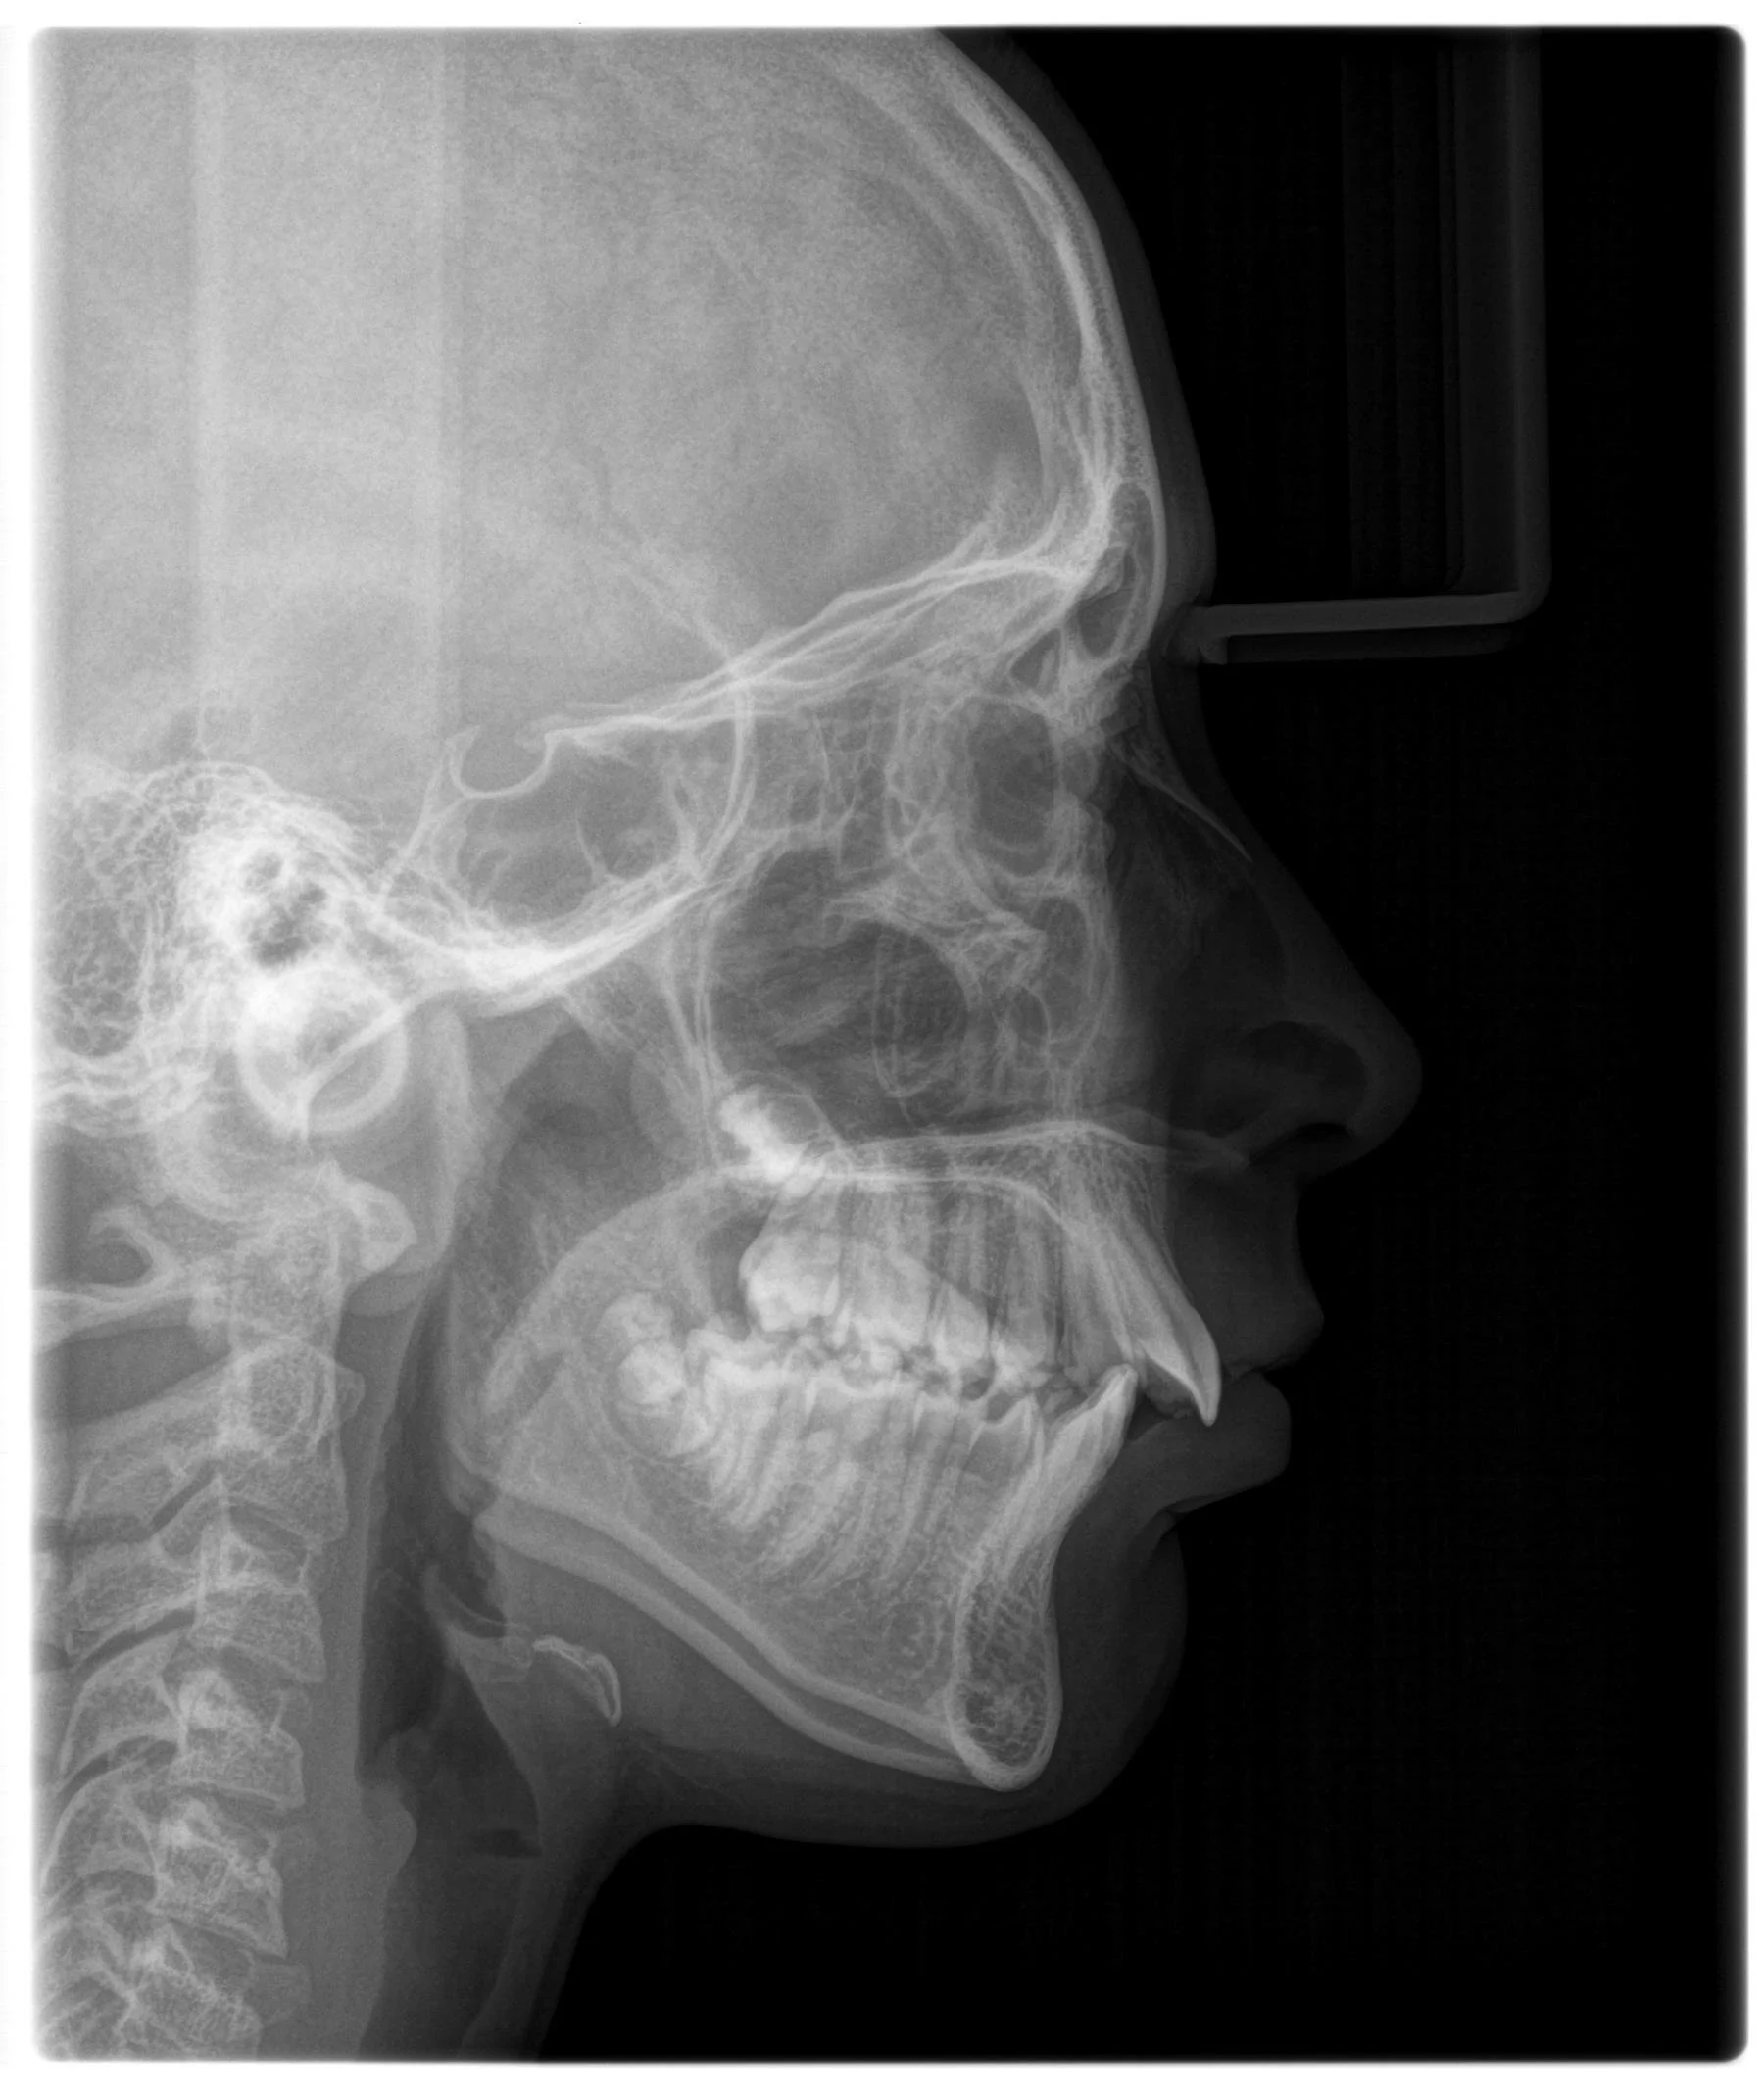

class III ceph.JPG